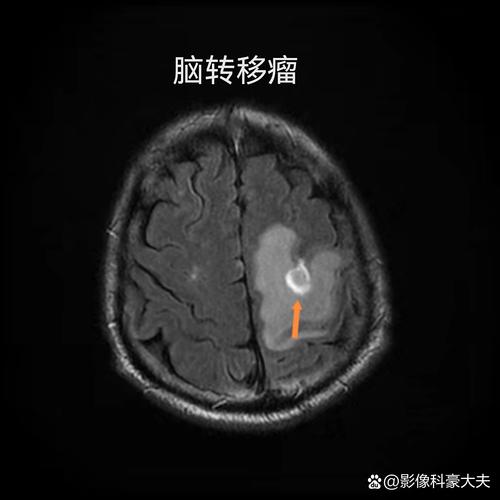

CT还可以帮助排除脑肿瘤、硬膜下血肿、脑脓肿等其他可能导致类似症状的疾病。

- 对小梗死灶不敏感:对于腔隙性脑梗(小血管堵塞),CT可能无法显示。

- 无法显示缺血半暗带:这是决定是否取栓的关键信息,普通CT看不出来,需要做磁共振成像。

磁共振成像,特别是DWI序列(弥散加权成像),对早期脑梗死非常敏感,在发病后30分钟到1小时就能发现病灶,是诊断早期脑梗的“金标准”。